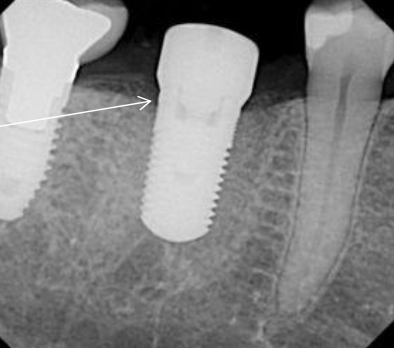

What is the success criteria for dental implants?

No implant mobility (No periodontal ligament)

No peri-implant radiolucency

Marginal bone loss not exceeding 0.2 mm after the first year

Absence of pain, infections, paresthesia or neuropathies

What are some methods to determine osseointegration?

Mobility

Clinical symptoms, pain when manipulated

Radiograph

Simple “tap” test (dull sound indicates lack of osseointegration)

Reversed torque-test using manual or electric torque device

Resonance Frequency Analysis- high frequency sonic energy (tuning fork)